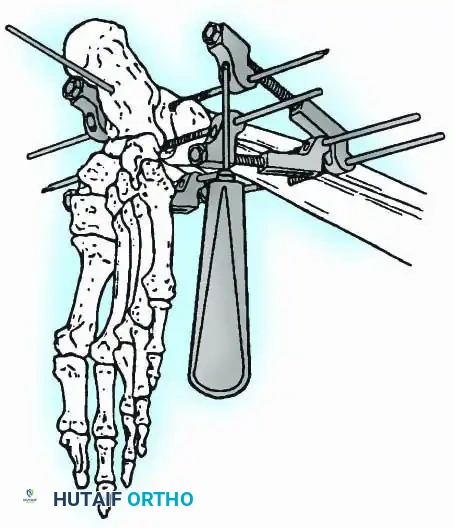

External Fixation

Historically pioneered by Charnley, external compression arthrodesis utilizes pins placed through the distal tibia and the body of the talus. Because Charnley's original uniplanar device lacked rotatory stability, Calandruccio designed a triangular frame to control motion in all three planes while applying massive compression.

Modern iterations, such as the Calandruccio II compression device, offer greater latitude in pin placement to avoid compromised skin. Ring or circular external fixators (Ilizarov, Taylor Spatial Frame) are the gold standard for salvage situations, including active infection, massive bone loss, or failed TAA, as they allow for simultaneous compression, deformity correction, and early weight-bearing.